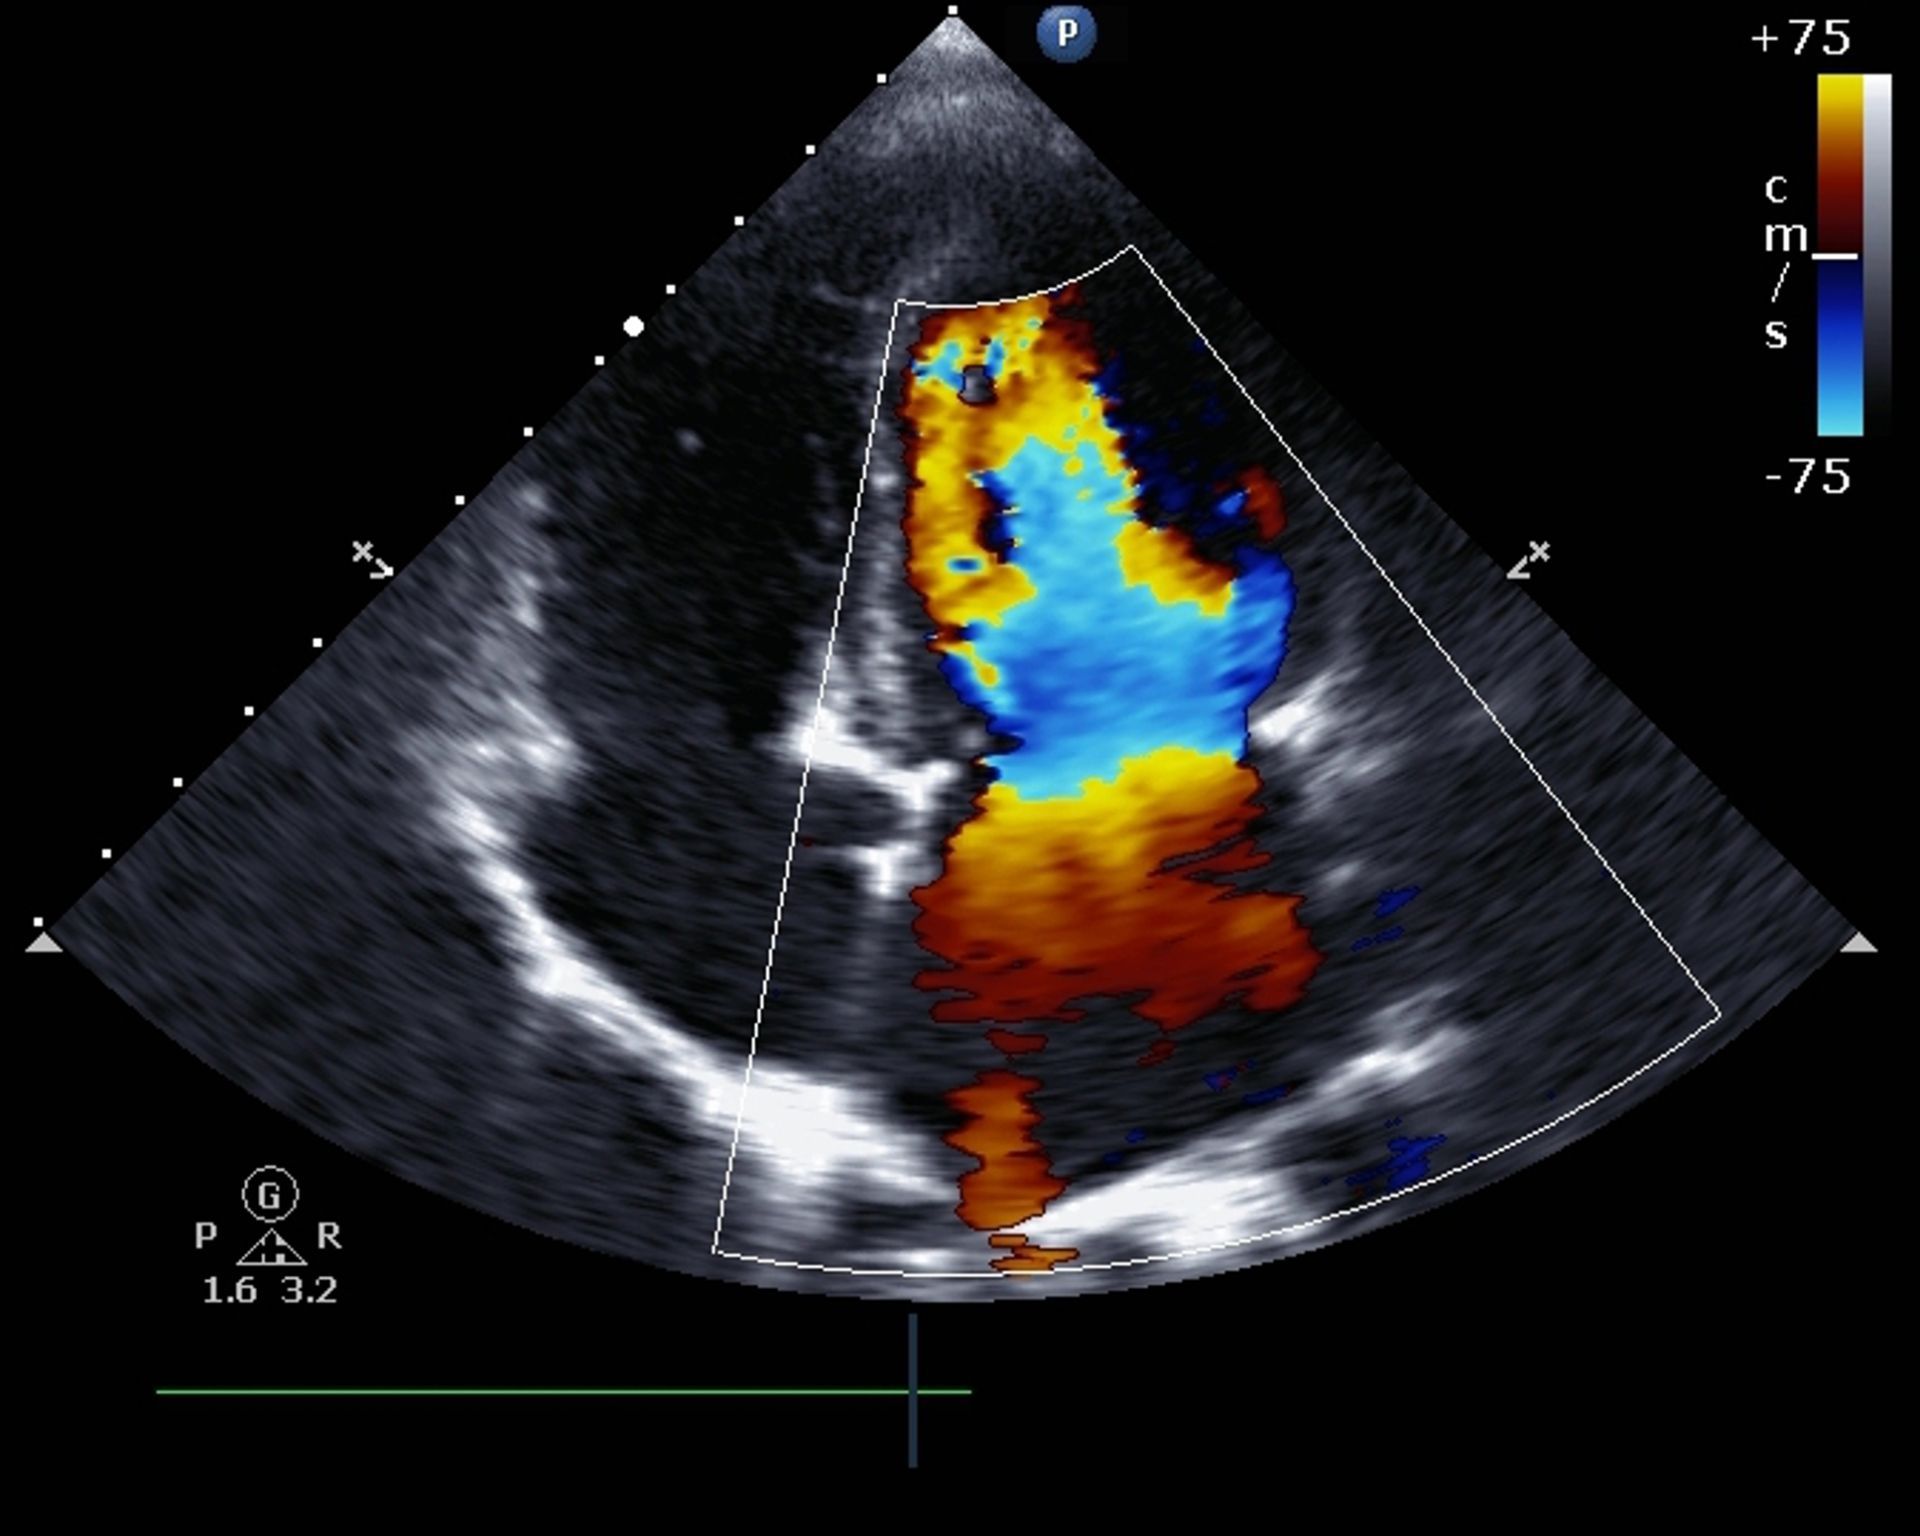

Sono infatti presenti diversi ambulatori di medicina specialistica per eseguire i seguenti test e visite: visite cardiologiche, ecocardiocolordoppler a riposo, elettrocardiogramma, elettrocardiogramma da sforzo, spirometria, holter, holter pressorio, cicloergometro sotto sforzo, test da sforzo, test massimale sotto sforzo.